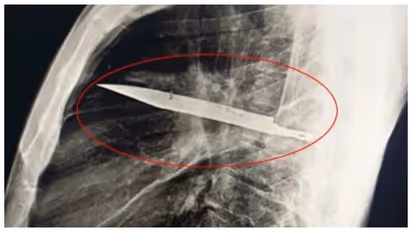

മുലക്കണ്ണില് നിന്നും പഴുപ്പ് വരുന്നതിന്റെ കാരണം തേടിയാണ് ഡോക്ടർമാര് എക്സ്റേ എടുക്കാന് നിർദ്ദേശിച്ചത്. എക്സ്റേയില് നെഞ്ചിന്റെ മധ്യഭാഗത്തായി ഒരു ലോഹ വസ്തു കാണാം. ശരീരത്തില് പ്രവേശിച്ച പുറത്ത് നിന്നുള്ള വസ്തുവിന് ചുറ്റും ചത്ത ശരീര കലകൾ അടിഞ്ഞ് കൂടിയതിന്റെ ഫലമായാണ് പഴുപ്പ് ഉണ്ടായതെന്ന് ഡോക്ടർമാര് വിശദീകരിച്ചു. പിന്നാലെ നടത്തിയ ശസ്ത്രക്രിയയില് പഴുപ്പും കത്തിയും പുറത്തെടുത്തു. 24 മണിക്കൂറോളം ഐസിയുവില് കിടത്തിയ രോഗിയെ പത്ത് ദിവസത്തോളം ജനറൽ വാർഡിലേക്ക് മാറ്റി. രോഗി സുഖം പ്രാപിക്കുന്നെന്ന് റിപ്പോര്ട്ടുകൾ കൂട്ടിചേര്ത്തു.